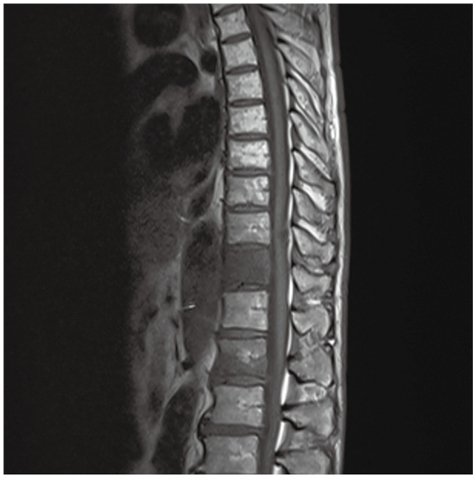

症例2

症例2の患者情報

70歳代,男性。

左下葉肺癌,多発リンパ節転移に対して化学療法中。腰痛を自覚し,胸腰椎MRI検査で異常を指摘された。

既往歴:右上葉肺癌(右肺上葉切除後),左上葉肺癌(左肺上葉部分切除後)。